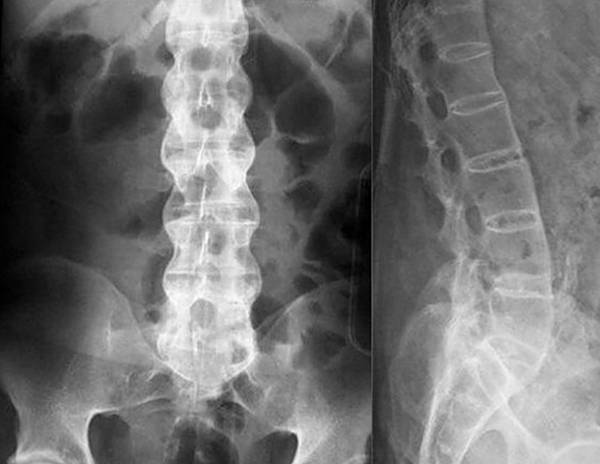

Если симптомы указывают на грыжу, остеохондроз или радикулит, для диагностики обычно используют рентгенографию. Этот метод прост и доступен, а время на получение снимка минимально, в отличие от компьютерной томографии (КТ), где требуется длительная неподвижность. Для оценки состояния сосудов и мягких тканей назначают УЗИ, а при подозрении на инфекцию проводятся лабораторные исследования крови и мочи. На основе полученных данных врач подбирает оптимальный способ лечения.

При заболеваниях позвоночника чаще всего используют рентгенографию для диагностики.